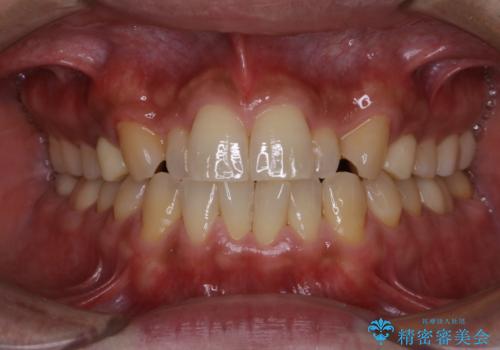

数年ぶりに歯のクリーニング(PMTC)